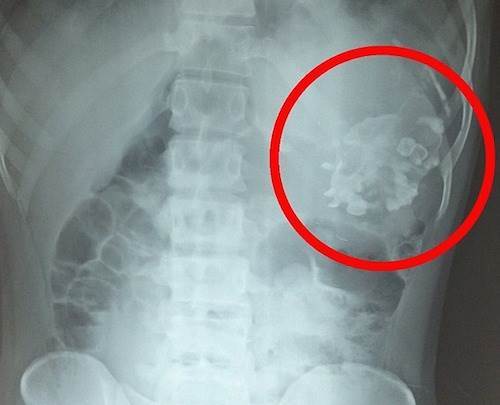

体内に弟が18年間寄生していた少年…手術して取り出した物体にショックを隠せない…